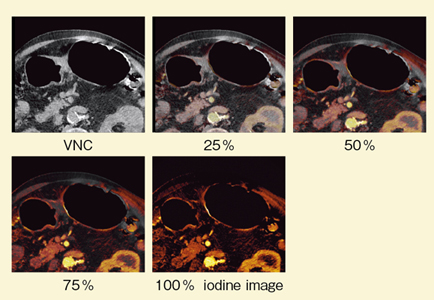

造影検査においては,Low-kVの方が圧倒的に造影剤の検出能が高いことが知られている。80kVではノイズが多いが造影剤のコントラストが高く,140kVではノイズは少ないものの造影剤のコントラストが低下しており,それらを合成した120kV相当では両方の特徴を合わせた画像を得ることができる。さらに,CT値によって合成の割合を変化させることで,optimum contrastも作成できる。CT値が低い部分では140kVと80kVのミックス画像を使い,濃度が高い部分では80kVの画像を使うblending法である。さらに,当院ではLiver VNC(virtual non-contrast)を用いて,胃のiodine imageを再構成している。その際,最新の被ばく低減技術"SAFIRE"を用いることで,より明瞭な画像を得ることができる。

症例1は,胃角部V型胃がんである。胃角部小彎側のやや後壁寄りに,かなり深い潰瘍が認められた。DEで撮影したところ,逐次近似画像再構成法であるSAFIREを併用したcomposite imageにて,病変部が最も明瞭に描出された(図1)。ダイナミックCTを施行したところ,動脈相では80kVで粘膜が,門脈相では80kVで腫瘍が最も良好に濃染した(図2)。また,Liver VNCでiodine imageを評価したところ,50〜100%の画像で胃壁が最も良好に濃染しているが,腫瘍は濃染していなかった(図3)。さらに,SAFIREを用いたcomposite imageでは,特に平衡相で,どの部分に多く造影剤が流入しているかが理解しづらい(図4)。そこで,iodine imageを作成したところ,門脈相から平衡相にかけて,後壁部分がきわめて良好に濃染していることがわかった(図5)。これにより,後壁中心に線維化の強い胃がんと診断できた。本症例は潰瘍があるため,深達度診断が難しいが,胃壁外の血管の拡張も明瞭に認められ,進行がんの可能性があると思われる。

![]() 図3 症例1:Liver VNCによるiodine/composite image |